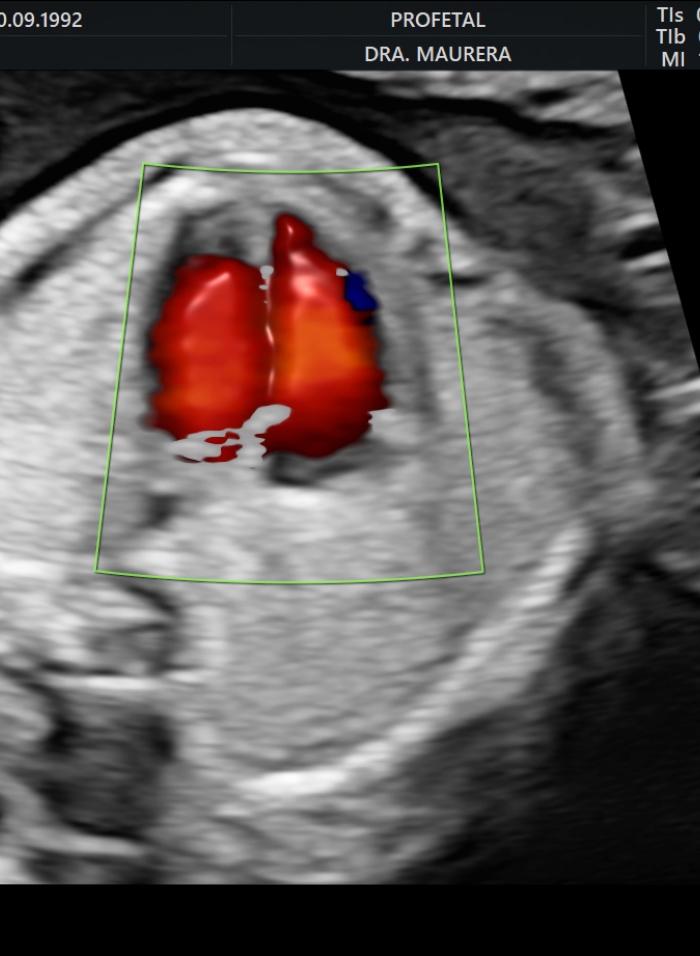

• Ecocardiografía Fetal (Semanas 24-28): Un estudio especializado del corazón fetal para descartar cardiopatías congénitas, especialmente en embarazos de alto riesgo.